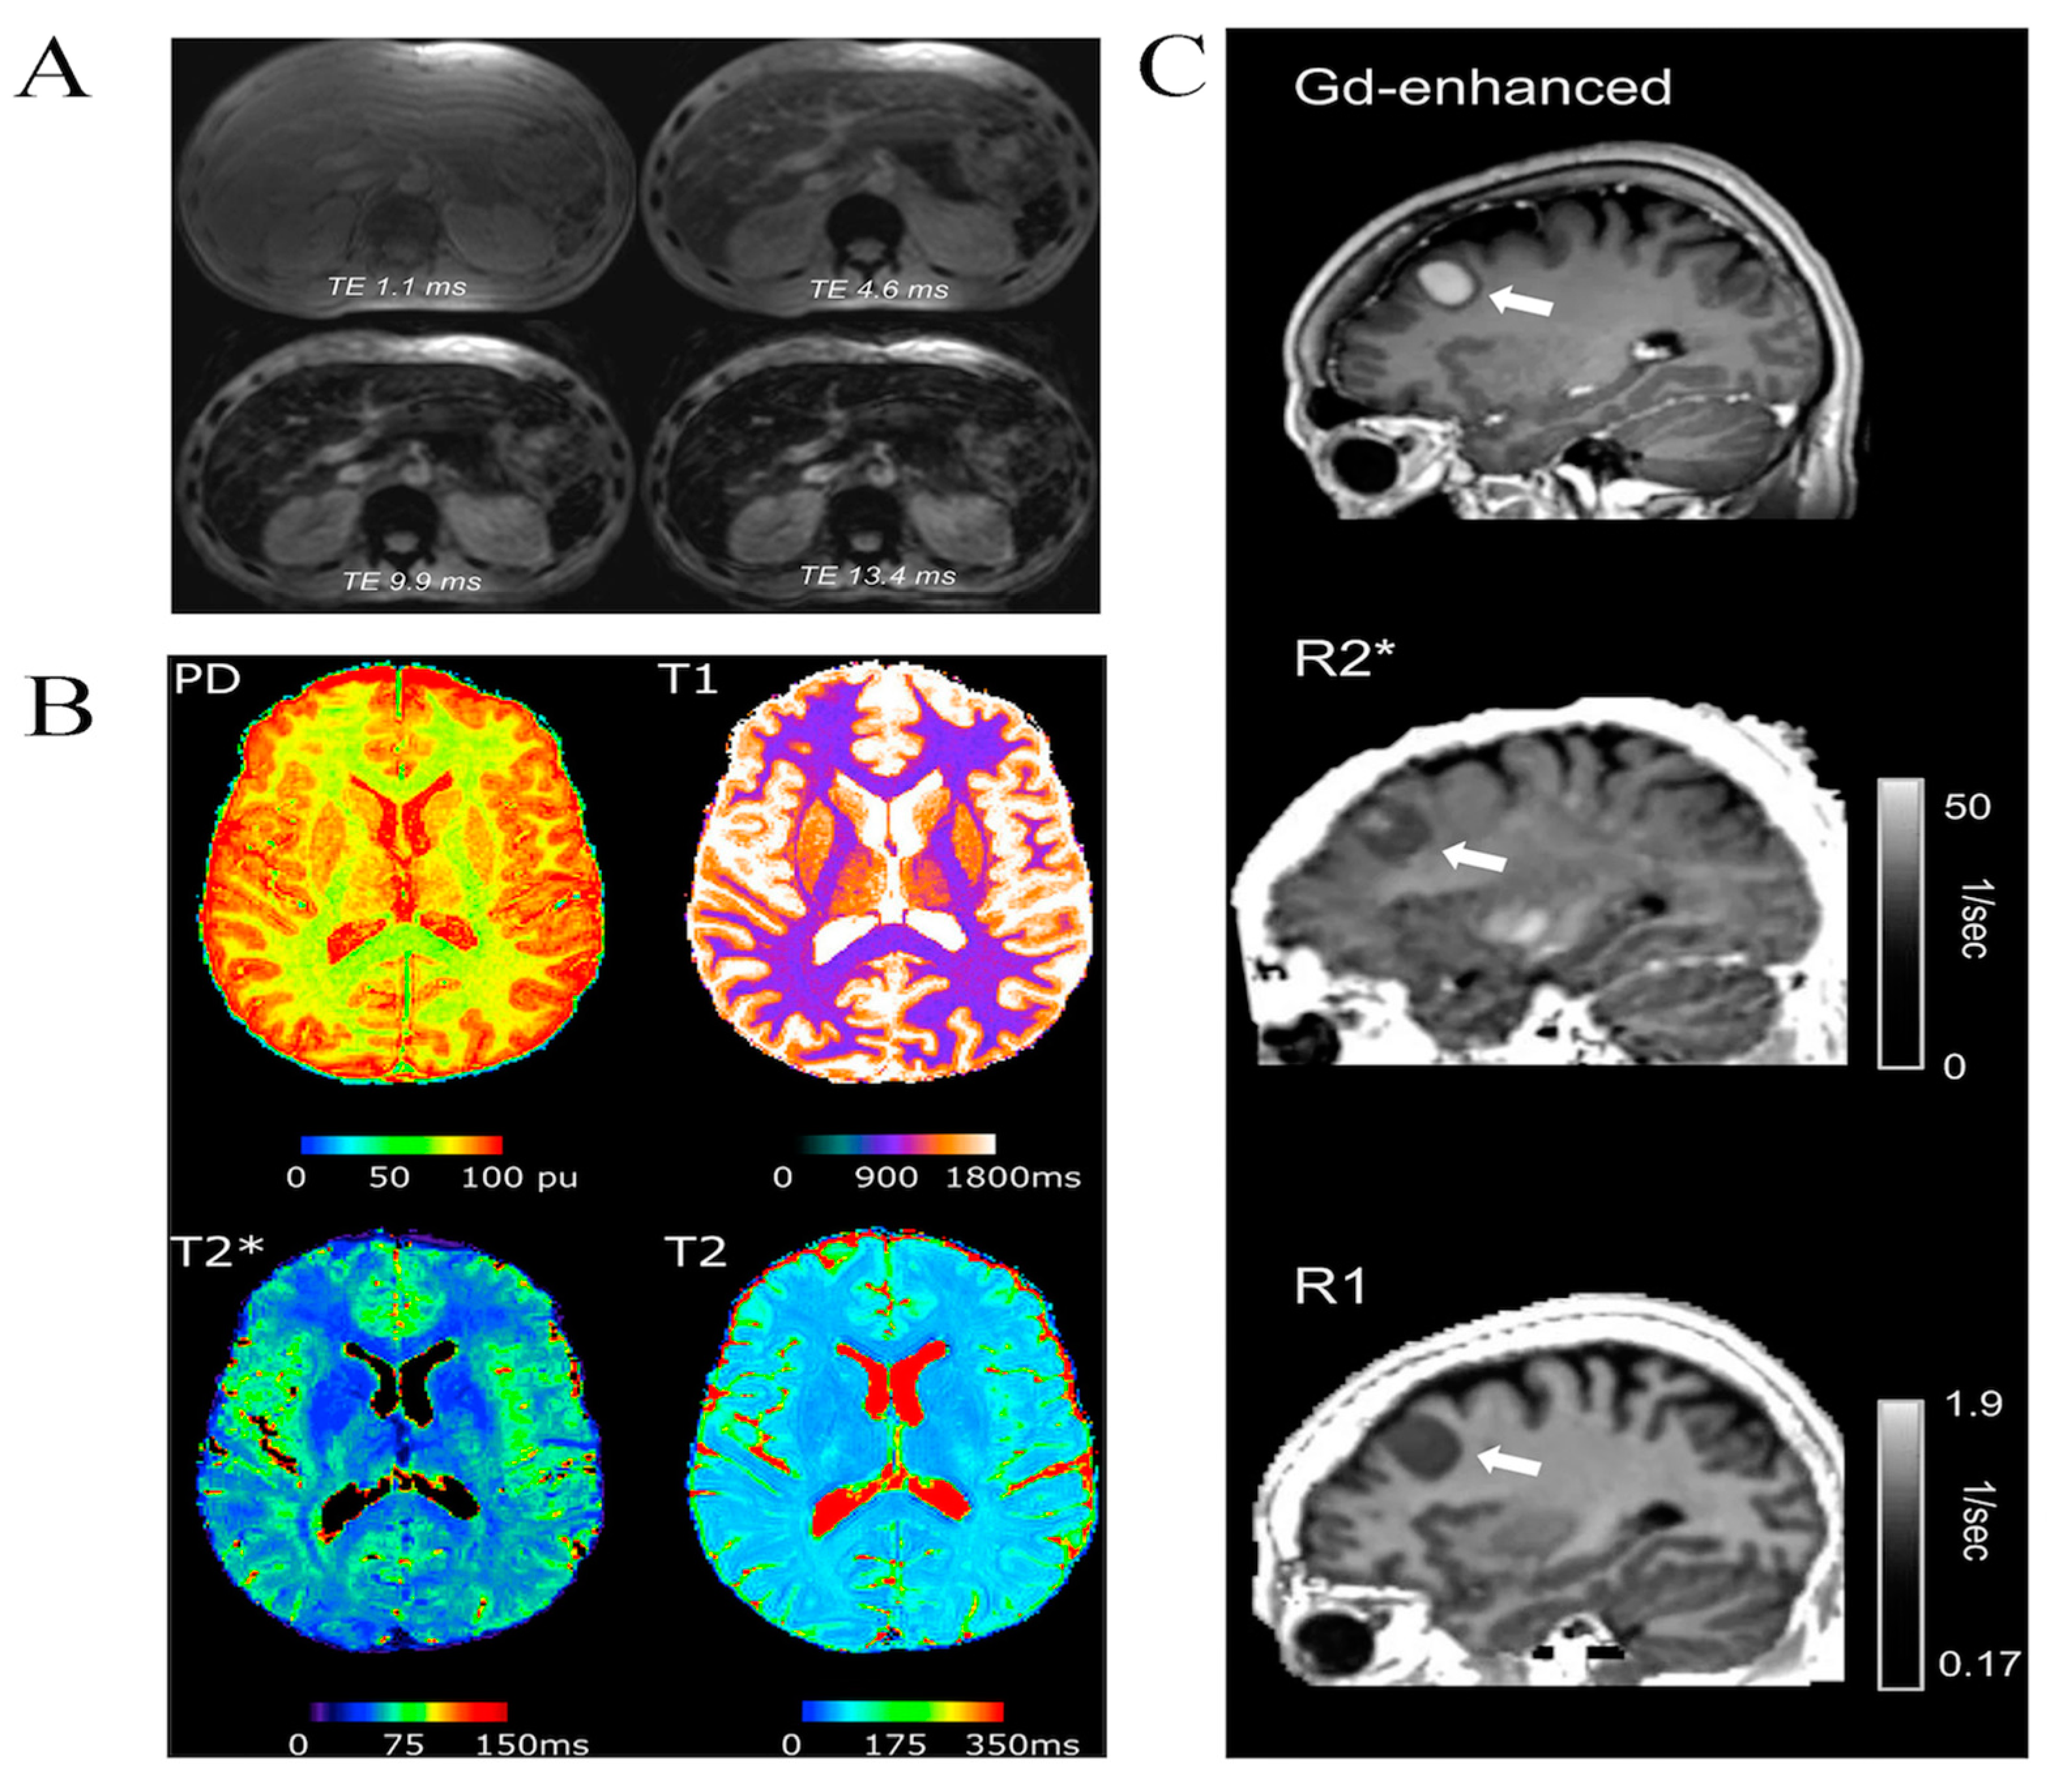

- Wood, J.C. Use of Magnetic Resonance Imaging to Monitor Iron Overload. Hematol. Oncol. Clin. N. Am. 2014, 28, 747–764. [Google Scholar] [CrossRef]

- Reeder, S.B.; Yokoo, T.; França, M.; Hernando, D.; Alberich-Bayarri, Á.; Alústiza, J.M.; Gandon, Y.; Henninger, B.; Hillenbrand, C.; Jhaveri, K.; et al. Quantification of Liver Iron Overload with MRI: Review and Guidelines from the ESGAR and SAR. Radiology 2023, 307, e221856. [Google Scholar] [CrossRef]

- Pierre, T.G.S.; Clark, P.R.; Chua-Anusorn, W.; Fleming, A.J.; Jeffrey, G.P.; Olynyk, J.K.; Pootrakul, P.; Robins, E.; Lindeman, R. Noninvasive measurement and imaging of liver iron concentrations using proton magnetic resonance. Blood 2005, 105, 855–861. [Google Scholar] [CrossRef]

- Sheth, S.; Allen, C.J.; Farrell, D.E.; Tripp, J.H.; Jafari, R.; Wang, Y.; Brittenham, G.M. Measurement of the liver iron concentration in transfusional iron overload by MRI R2* and by high-transition-temperature superconducting magnetic susceptometry. Clin. Imaging 2019, 55, 65–70. [Google Scholar] [CrossRef] [PubMed]

- Alustiza, J.M.; Castiella, A.; Zapata, E.; Urreta, I.; Salvador, E.; Emparanza, J. Non-invasive measurement of liver iron concentration by magnetic resonance imaging and its clinical usefulness. Arch. Med. Sci. AMS 2023, 19, 784. [Google Scholar] [CrossRef] [PubMed]

- Idilman, I.S.; Akata, D.; Ozmen, M.N.; Karcaaltıncaba, M. Different forms of iron accumulation in the liver on MRI. Diagn. Interv. Radiol. 2016, 22, 22–28. [Google Scholar] [CrossRef] [PubMed]

- Sirlin, C.B.; Reeder, S.B. Magnetic Resonance Imaging Quantification of Liver Iron. Magn. Reason. Imaging Clin. N. Am. 2010, 18, 359–381. [Google Scholar] [CrossRef] [PubMed]

- Ahmed, A.; Baldo, A.; Sulieman, A.; Mirghani, H.; Abolaban, F.A.; Suliman, I.I.; Salih, I. Optimisation of T2 and T2* sequences in MRI for better quantification of iron on transfused dependent sickle cell patients. Sci. Rep. 2021, 11, 8513. [Google Scholar] [CrossRef]

- Wood, J.C.; Enriquez, C.; Ghugre, N.; Tyzka, J.M.; Carson, S.; Nelson, M.D.; Coates, T.D. MRI R2 and R2* mapping accurately estimates hepatic iron concentration in transfusion-dependent thalassemia and sickle cell disease patients. Blood 2005, 106, 1460–1465. [Google Scholar] [CrossRef] [PubMed]